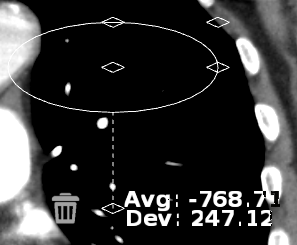

The Hounsfield annotation tool creates a region of interest and calculates its average pixel value and the standard deviation on the distribution.

To obtain a Houndsfield Value measurement:

Select the

Hounsfield Value  icon

icon

Click on the region of interest

Drag on the mouse to encircle the area

Release the mouse button

The default region of interest drawn on the image is a true circle. When resizing the ROI, maintain a true circle by using the corner grab points

The center grab point  will move ROI around the image and others will elongate

or narrow.

will move ROI around the image and others will elongate

or narrow.